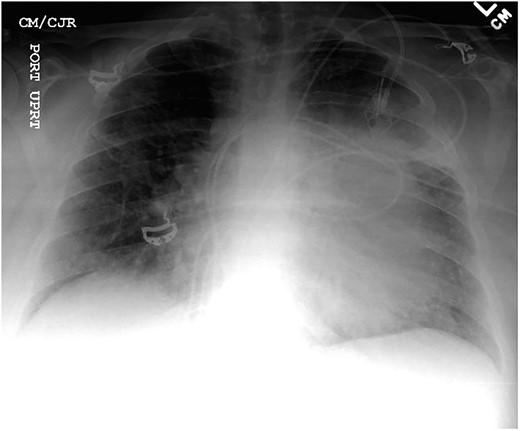

Chest X-ray found an enlarged cardiomediastinal silhouette with mild pulmonary edema (Fig. 1). A computed tomography angiography (CTA) of the chest to rule out pulmonary embolism (PE) was ordered. After the patient returned from imaging, she was found to have a heart rate of 178. Patient was awake, did not appear to be in any more distress and remained hemodynamically stable. Repeated ECG showed monomorphic ventricular tachycardia, with the patient remaining non-distressed. Patient was started on i.v. amiodarone, and urgent cardiology consult was obtained. A transthoracic echocardiogram depicted a large mass measuring 5 cm by 7 cm occupying the basal and mid portion of the anterior and lateral walls of the left ventricles with large pericardial effusion located at the lateral posterior wall of the heart, findings suggestive of impending tamponade (Fig. 2). CTA of the chest reported no acute PE with a large mass (10.5 × 7.5 × 9.5 cm3) occupying the anterior wall of the left ventricle and extending to the pulmonary outflow tract (Fig. 3).

Anterior–posterior one view chest X-ray depicting enlarged cardiomediastinal silhouette with mild pulmonary edema.